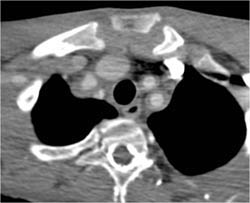

Takayasu's Arteritis